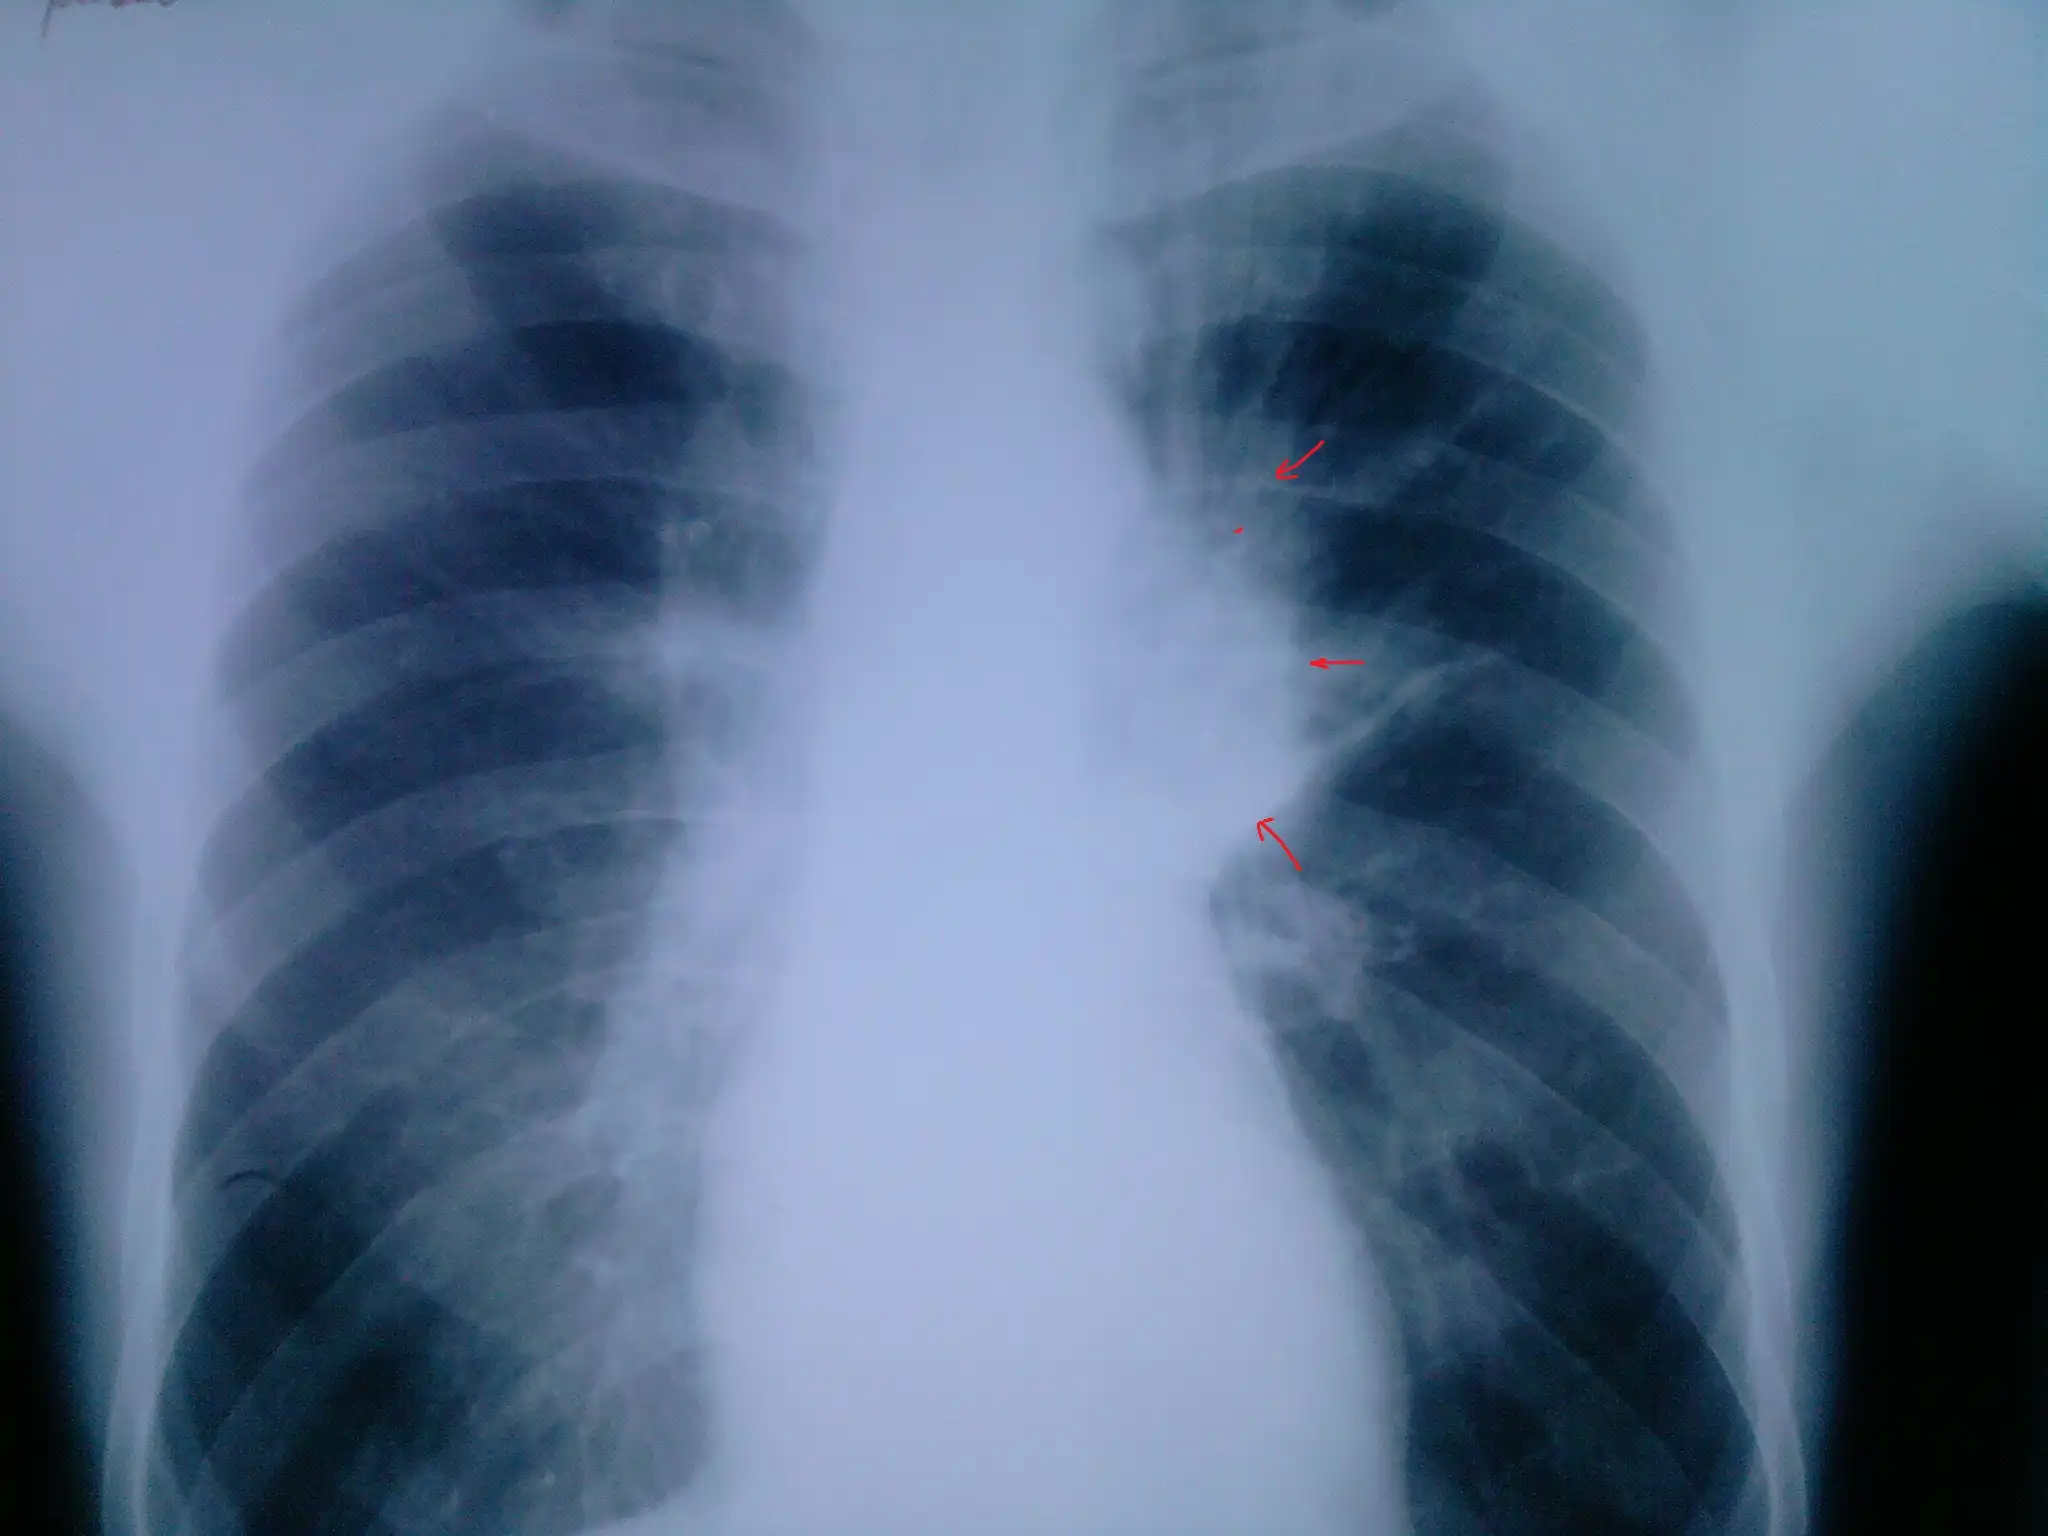

Пациент №2:

Флюорограмма:

2. По поводу снимков... Сомнение вызывает первый пациент. 2 фокуса в разных легких... Разве что метастазы в прикорневые л\у правого легкого... Да и контуры очень четкие в левом легком... Верхняя доля... Дорожка к корню... Больше похоже на туберкулез ИМХО. Хотя и лучистость есть... Спорно.

Пациенты 6 и 7 тоже под вопросом... Не четкая картина.